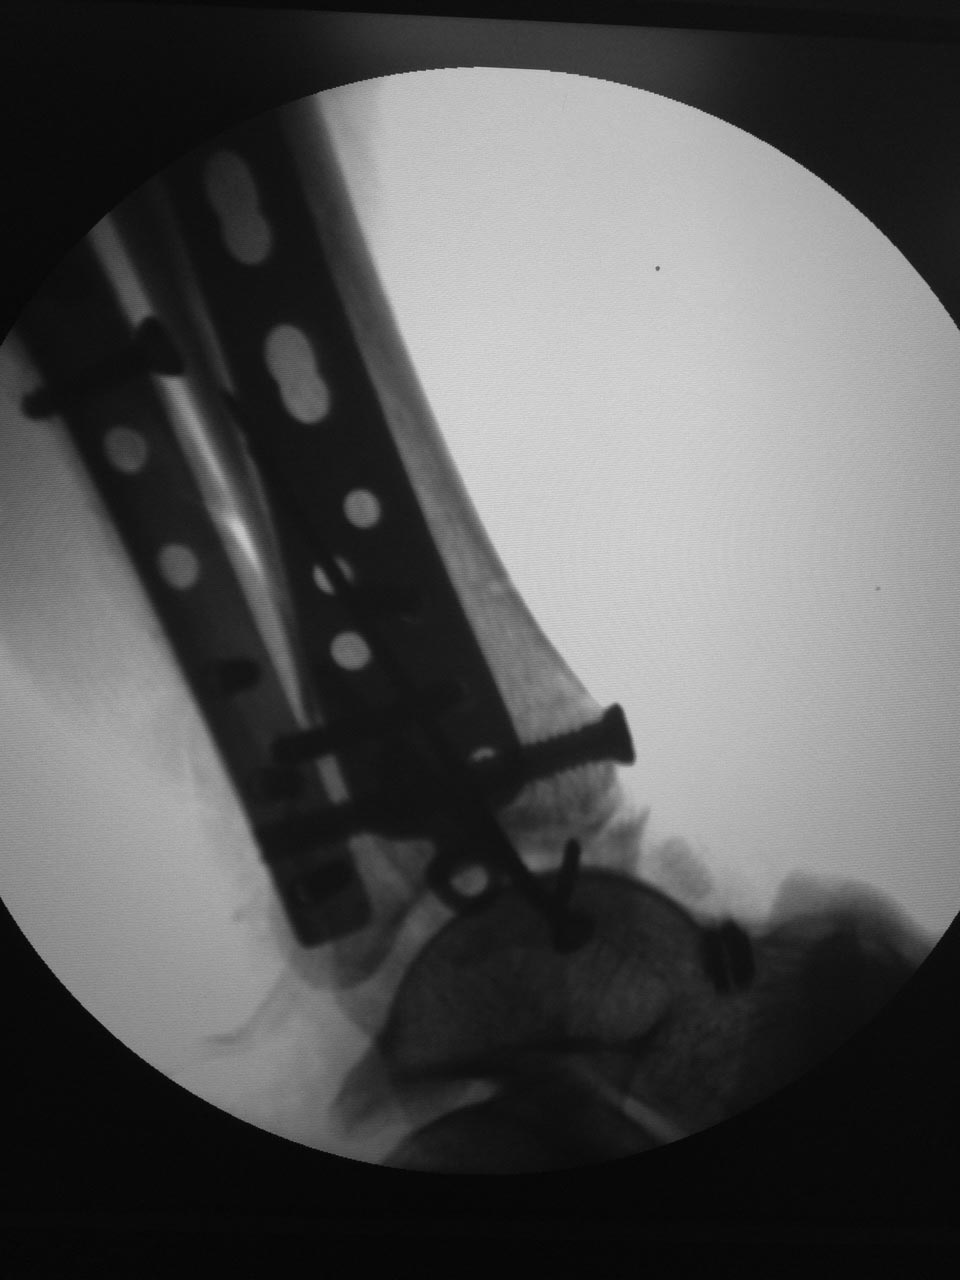

Дмитрий 19 Декабрь 2015, 00:55

Результат.

Отправитель: Дмитрий 19 Декабрь 2015, 07:53

Считаю результат удовлетворительным, начали все-таки с м/берцовой, после её фиксации задний край встал. Вторым доступом был задне-медиальный здесь обнаружился не связанный с диафизом и значительный по величине метаэпифизарный передне- медиальный отломок, его временно фиксировал спицами, затем провёл фиксацию внутренней лодыжки к этому фрагменту также спице, задний край фиксировали винтами, далее медиальная пластина, м/инвазивно(насколько возможно), затем винт во внутреннюю лодыжку. После этого проверил синдесмоз, он оказался состоятелен. На счёт что это за перелом: если бы не один передне-медиальный фрагмент, который по-суть захватывает 40-50% суставной поверхности, то без сомнений это 4 4, а так все-таки 4 3, но синтез м/берцовой считаю в этом случае был необходимым и первоочерёдным ). P.S: спасибо всем за советы, очень помогло в планировании.

Это правильно, что с малоберцовой начали и фиксировали её. Задний край, медиальный отдел. Проверка стабильности-Все ок. Правда, медиальная лодыжка кажется недорепонировпнной.

Дмитрий, по снимку не понятно, какие винты какую функцию выполняют. Есть ли винты стягивающие? Если есть, то какие?

Отправитель: Дмитрий 19 Декабрь 2015, 20:32

По суставной отрепонирована была ad ocullus, на снимках может так смотреться в следствие оскольчатого характера, стягивающий винт в пластине 4,5 мм один. Не рискнул ставить стягивающие в "ложку" побоялся "раздавить".